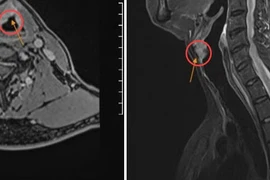

Khi xuất hiện các dấu hiệu như đau cổ kéo dài, đau lan xuống vai hoặc cánh tay, tê bì tay chân, yếu tay, người bệnh nên đến cơ sở y tế để được thăm khám sớm.